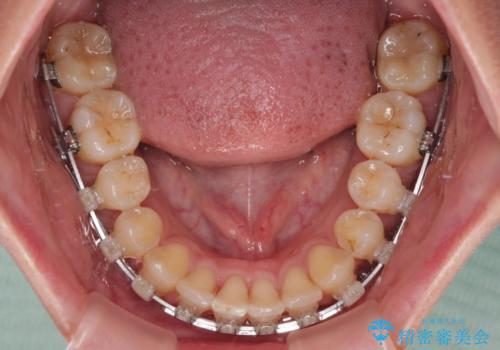

- クリアブラケット

- 1年6ヶ月

- 10-30回